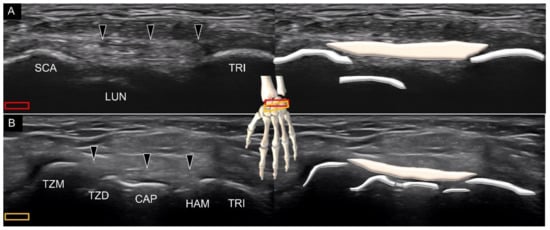

2. Sonoanatomy of Carpal Bones

3.3. Attachment to the Triquetrum

Attachment to the Triquetrum